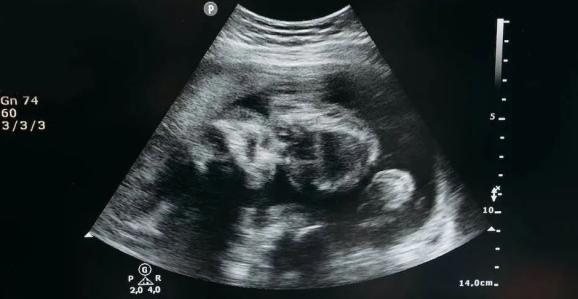

宝宝在妈妈肚子里,第8周听力器官开始发育,到20周左右已经基本完善,到孕晚期接近成人。